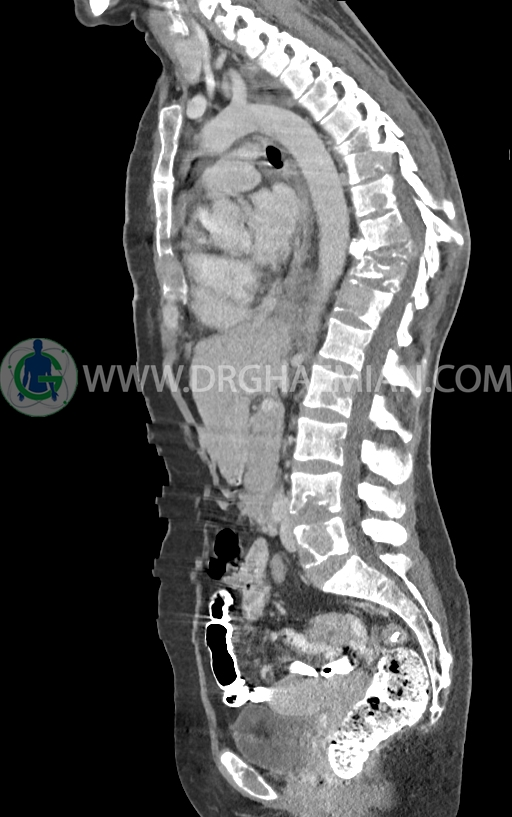

در سی تی اسکن اسپیرال ریه و مدیاستن -شکم و لگن با کنتراست خوراکی و وریدی (مولتی دیدکتور 16 با مقاطع ظریف و بازسازی های ساژیتال و کرونال) :

–توده نسج نرمی بسیار بزرگ به حداکثر دیامتر 82mm همراه با مارژین لبوله در پستان راست دیده شد که همراه با گسترش و درگیری پوست و نیپل بوده و مطرح کننده ضایعه تومورال و بدخیم می باشد.

–این توده در قسمت هایی عضله پکتورالیس این سمت را abut کرده است.

–افزایش ضخامت نسج نرمی و ندولاریته در پلور مدیال ریه چپ یا شاید مربوط به قسمت پره واسکولار مدیاستن با حداکثر ضخامت 10mm در level سوپراهیلار چپ دیده می شود که می تواند مشکوک برای لنفادنوپاتی یا متاستاز باشد.

–لنفادنوپاتی در هیلوم چپ وفضاهای مدیاستن دیده می شود بزرگترین آن ها با SAD=11mm در پره تراکئال دیستال و SAD=14mm در هیلوم چپ و 11mm در ساب کارینا دیده شدند

–پلورال افیوژن وسیع دو طرفه

–ضایعات استخوانی لیتیک فراوان منتشر در تمامی طول ستون مهره و لگن رویت شدند که مطرح کننده متاستاز استخوانی می باشند.